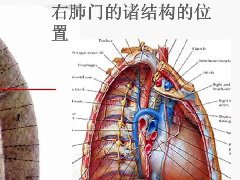

肺隔离症:易误诊为肺癌的占位性病变,肺穿刺禁忌!  肺段与肺内管道应用解剖